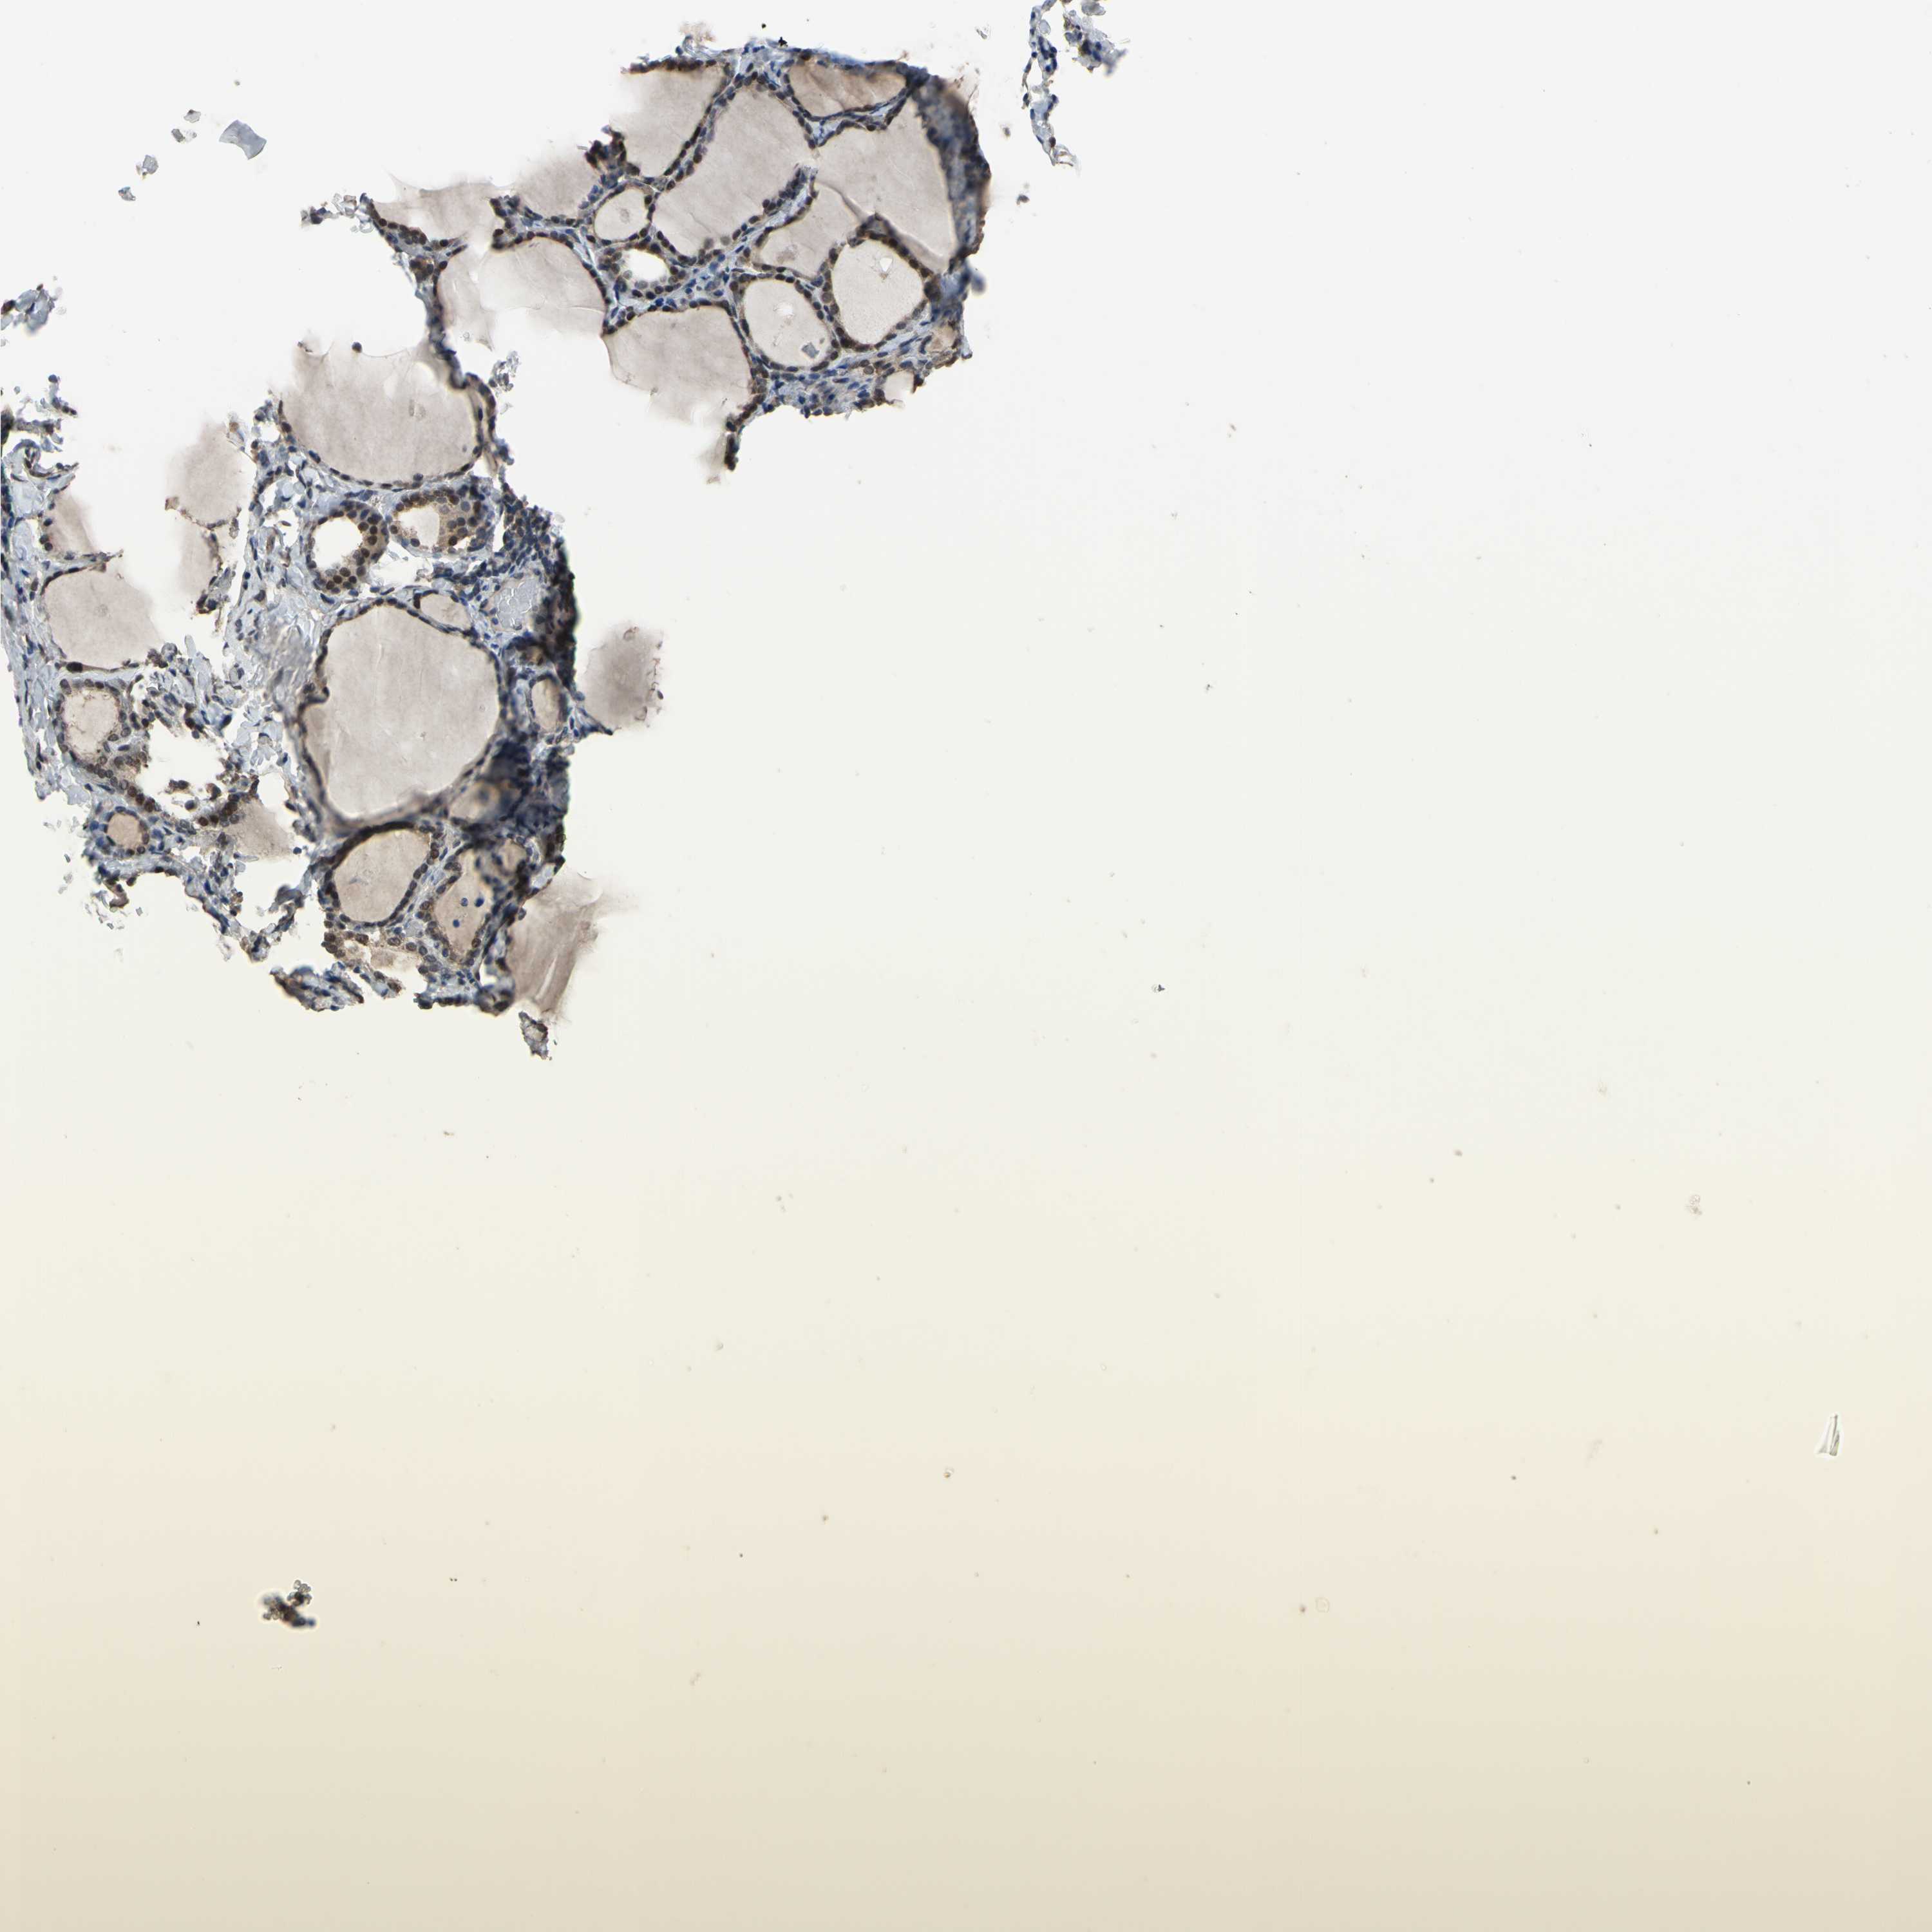

THYROID GLAND - Antibody stainingi

Antibody staining in the annotated cell types in the current human tissue is reported as not detected, low, medium, or high, based on conventional immunohistochemistry profiling in selected tissues. This score is based on the combination of the staining intensity and fraction of stained cells.

Each image is clickable and will lead to virtual microscopy that enables deeper exploration of all samples and also displays staining intensity scores, fraction scores and subcellular localization as well as patient and tissue information for each sample.

Antibody HPA009656

Glandular cells Medium